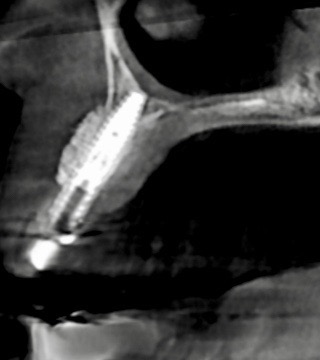

骨量不足でこのままではインプラント治療をお受けできない場合など専門性高い治療を当医院ではお受け致しております。